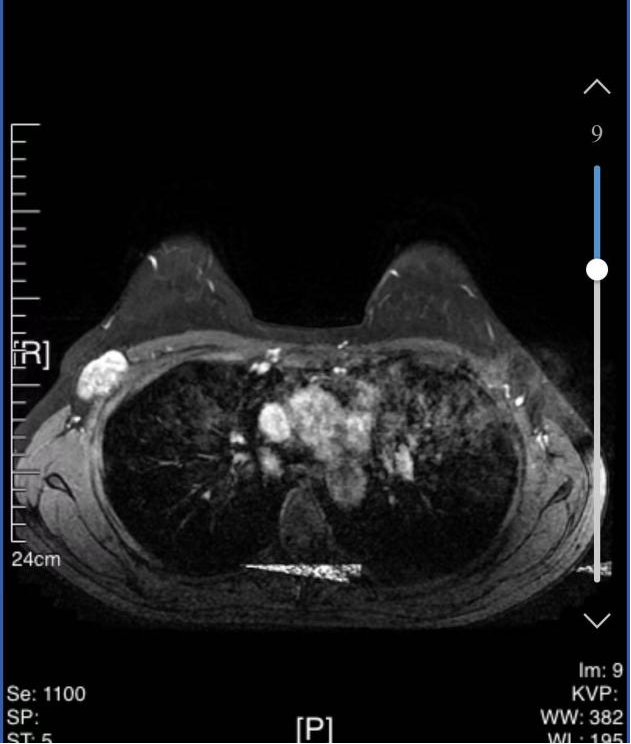

• 乳腺核磁共振(MRI):

1、右乳外侧象限见T2WI稍高信号肿物,大小约31mm*25mm*33mm,形态不规则,边缘分叶;内部强不均匀,TIC曲线初始呈快速强化,延迟期呈平台型;DWI呈高信号,ADC值为0.000811mm2/s。右腋窝见肿大淋巴结。

MRI提示:右乳外侧象限肿块及多处非肿块样强化,BI-RADS 5类;右腋窝淋巴结肿大。

图3 乳腺MRI结果(2024-03-04)